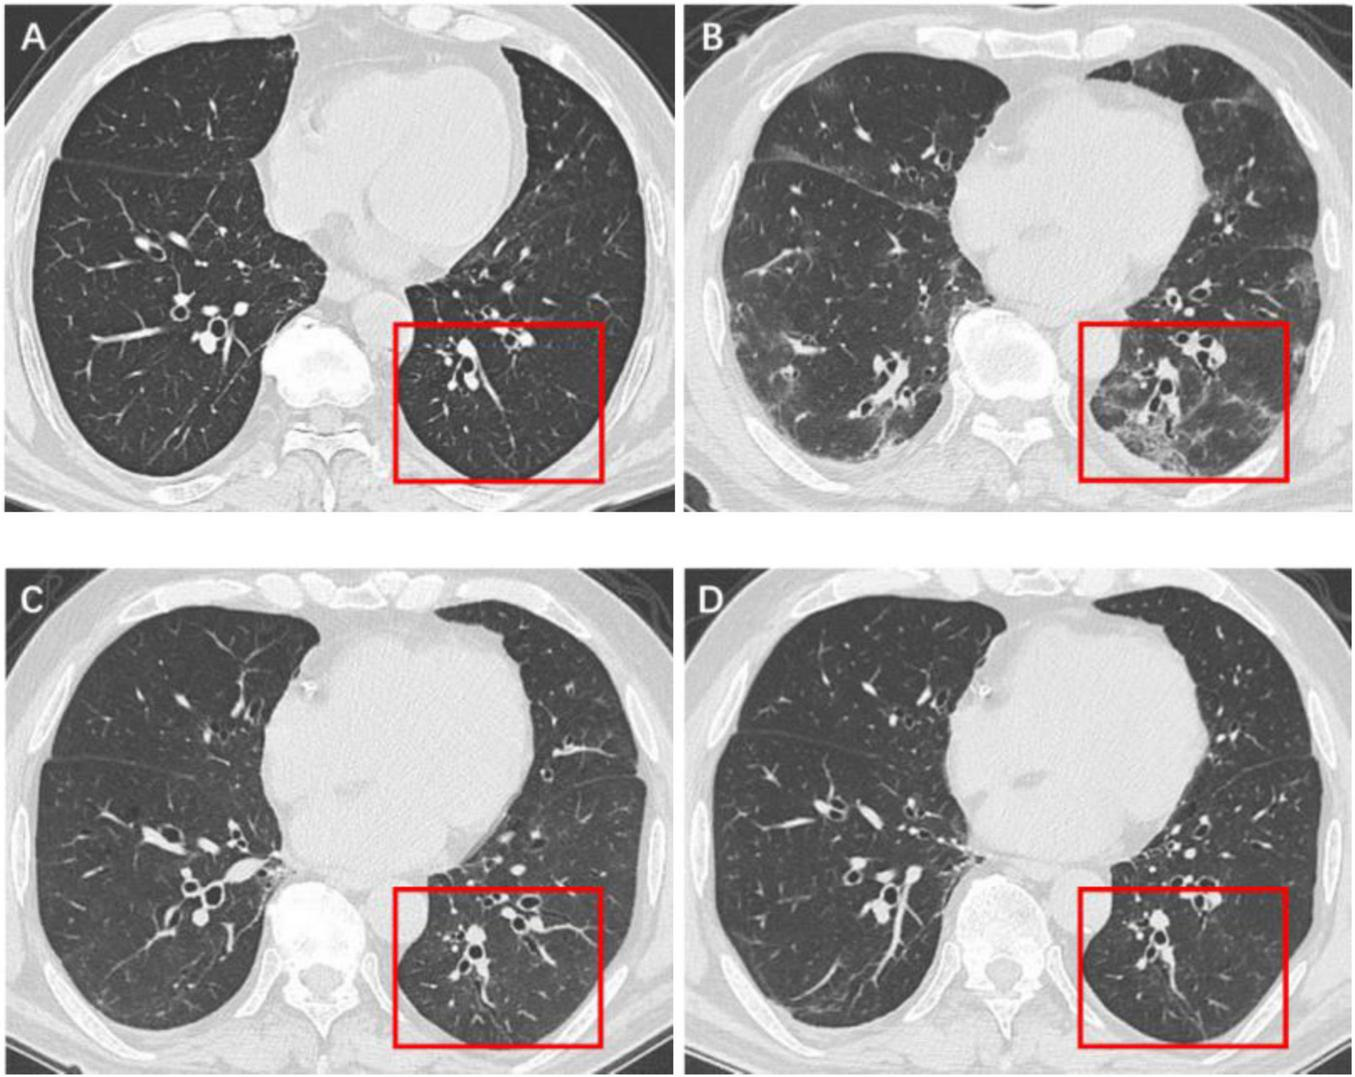

FIGURE 3

Serial high-resolution noncontrast chest CT in a 61-year-old man with COVID-19 pneumonia. (A) Health screening chest CT 3 months prior to COVID-19 infection showed no abnormalities in the lower lobe of left lung (red box). (B) Initial CT scans obtained on day 6 after the onset of symptoms showed multiple GGOs and reticulation (red box). (C) CT scans obtained on day 173 showed localized residual bronchiolectasis (red box). (D) CT scans obtained on day 375 showed persistence of the bronchiolectasis (red box).